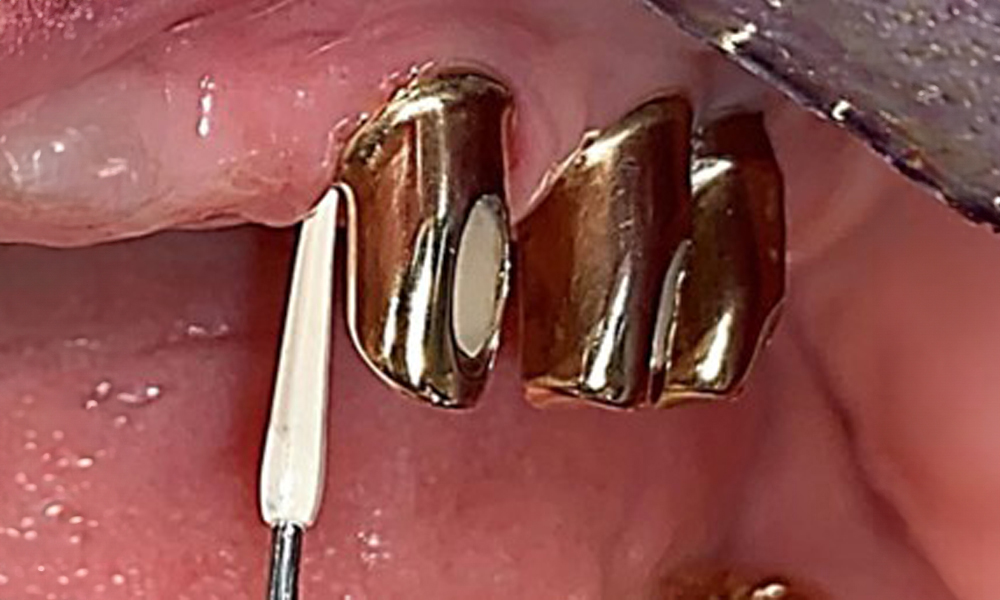

IPC cycle icon: magnifying glass

Based on the medical history, the risk of complications is classified as mild to moderate due to the intake of ASA 100 and bisoprolol. It should be noted that increased bleeding may occur during treatment, particularly if gingivitis is present. The risk is classified as low in the present case, as the patient maintains excellent intraoral hygiene. Due to the otherwise stable intraoral status over many years, the needs determined during the intraoral examination will be decisive for her treatment. The findings observed during any dental appointment will determine the subsequent course of treatment. Determination of bleeding status is mandatory to detect gingival changes in peri-implant tissues (Fig. 6).

Probing implant 23 at a probing depth of 4 mm using a plastic probe, showing negative BOP findings and a hyperplastic papilla.

Fig. 6: Probing implant 23 at a probing depth of 4 mm using a plastic probe, showing negative BOP findings and a hyperplastic papilla.

The periodontal status should be thoroughly examined once a year. This examination provides comprehensive documentation of the periodontal and implant findings, including pocket depths, periodontal recession and furcation involvement. This will ensure a rapid response to any potential progression of the mucositis, gingivitis, periodontitis or peri-implantitis. Implant probing using a plastic probe is recommended. In the present case, a mesial probing depth of 4 mm was detected mesial to implant 23. No suppuration or bleeding was detected, indicating the absence of peri-implantitis.